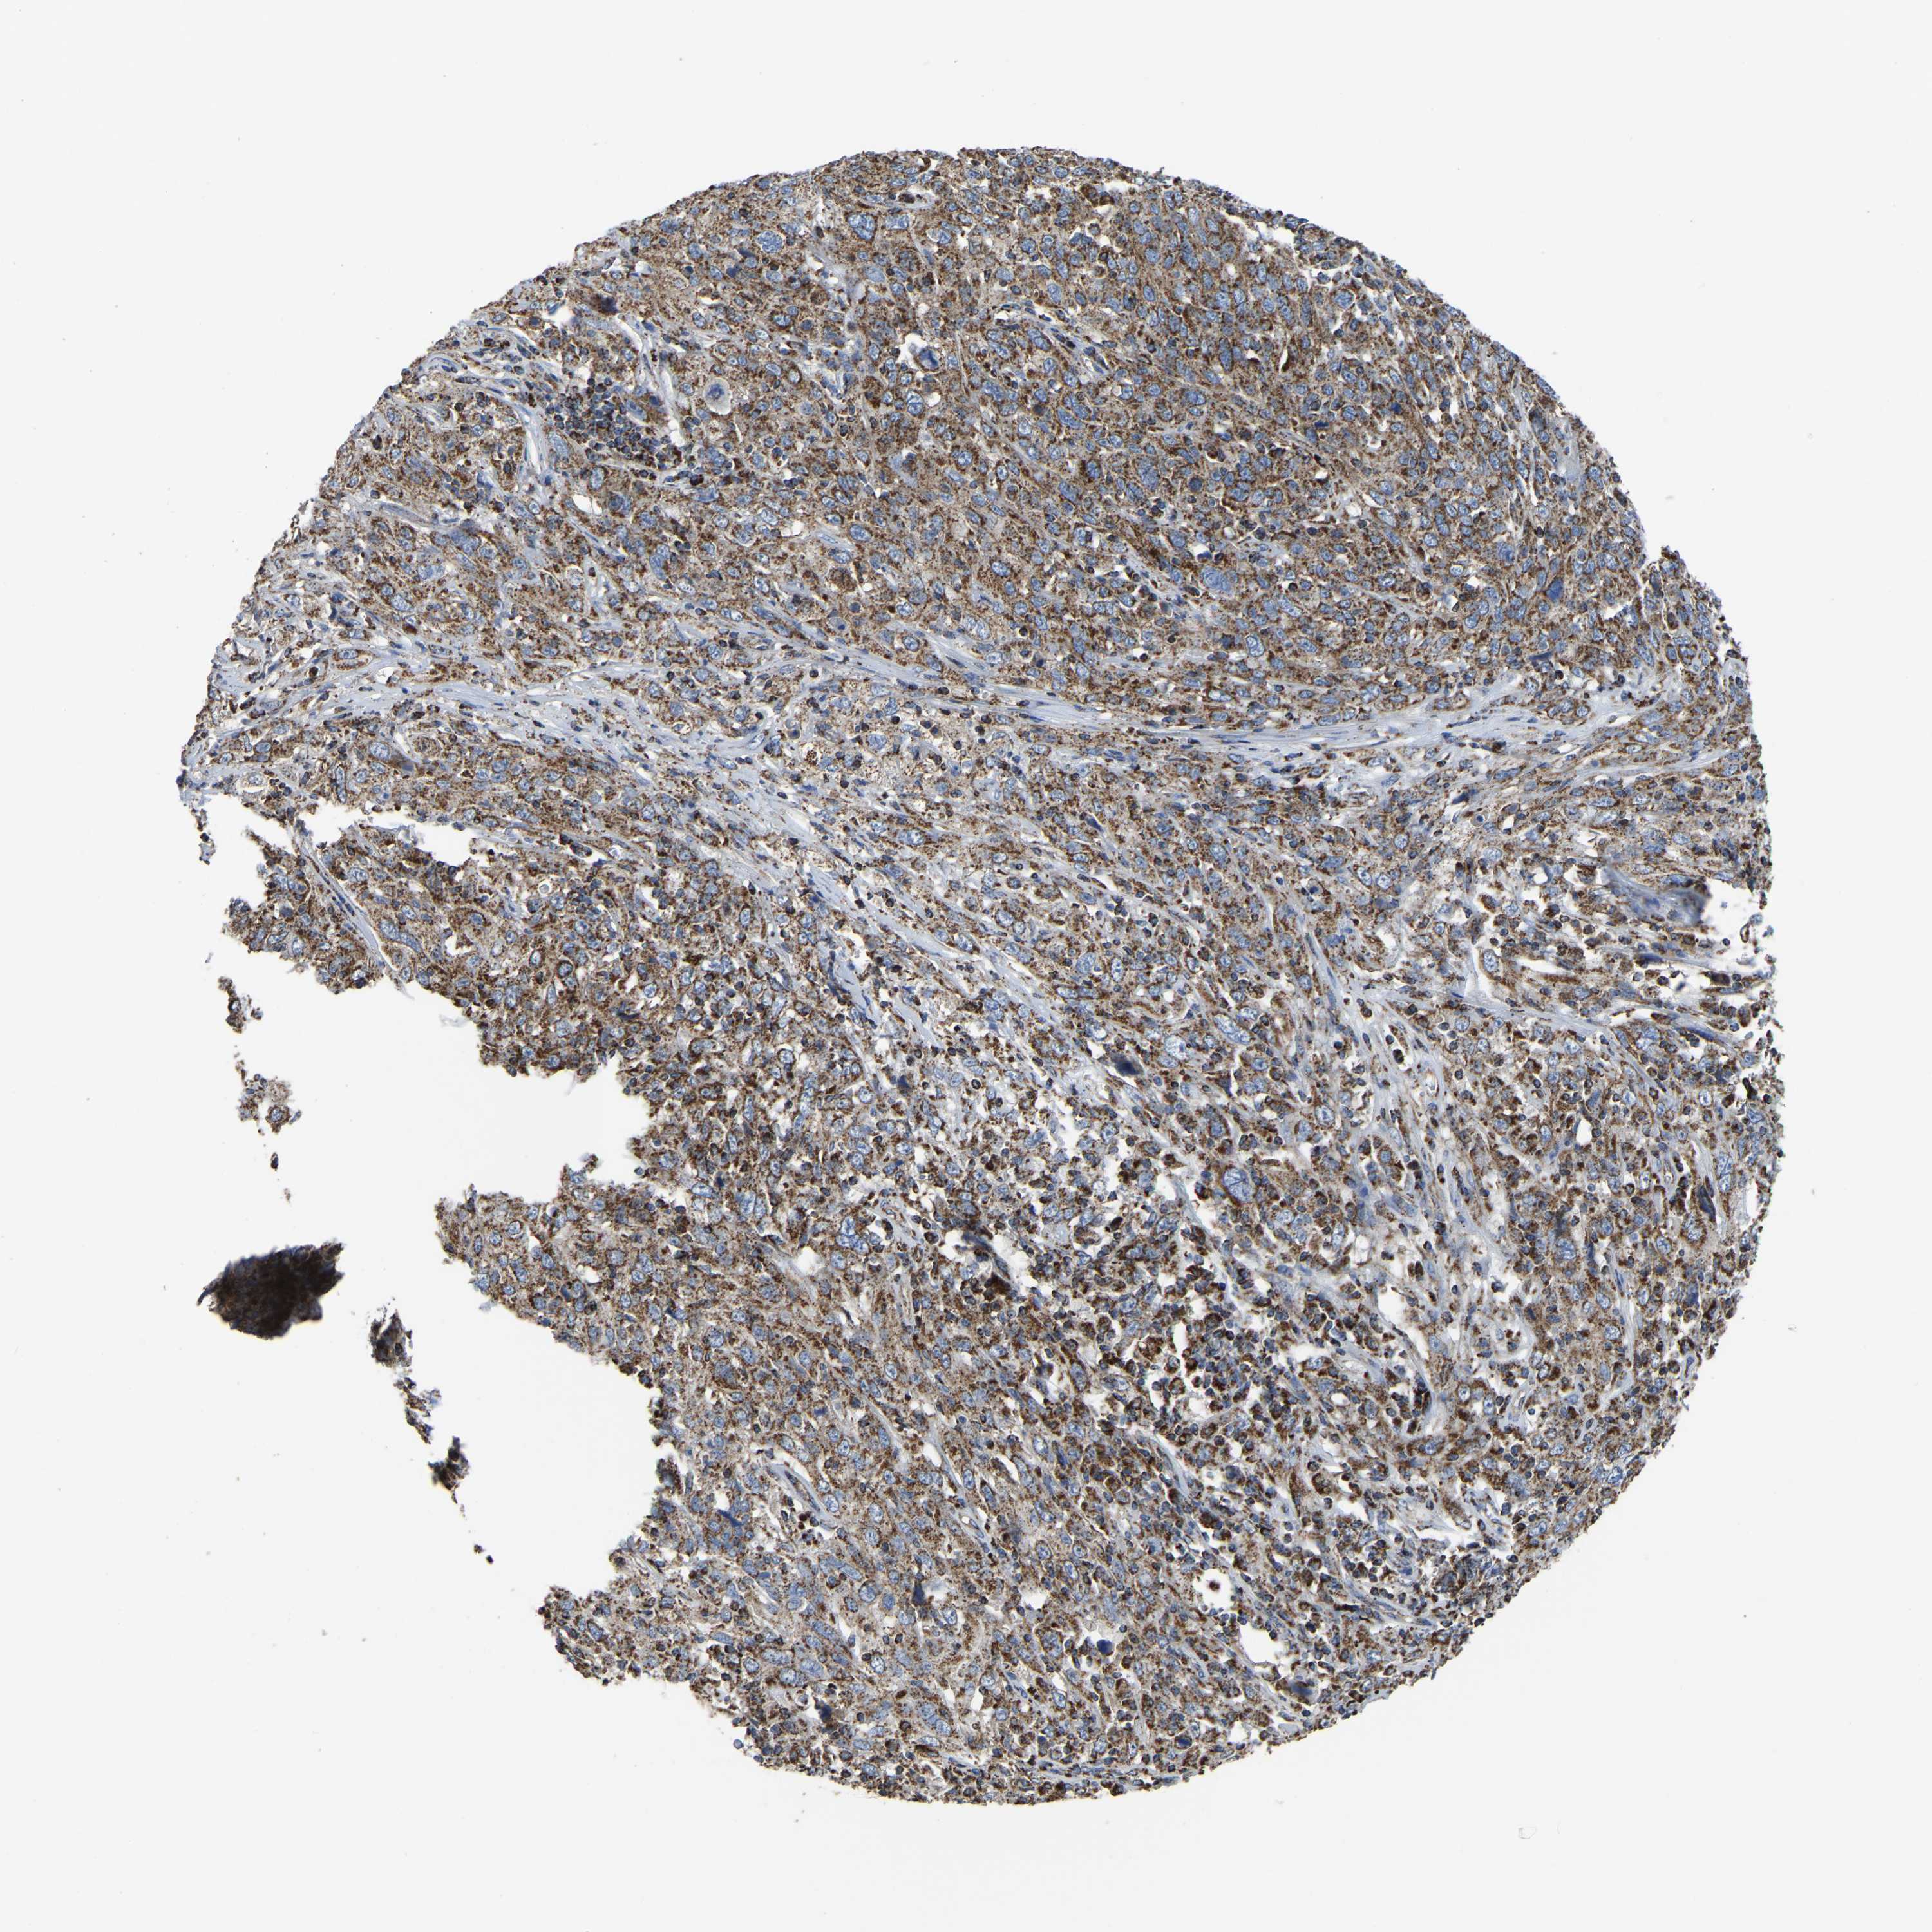

CERVICAL CANCER - Protein expressioni

A mouse-over function shows sample information and annotation data. Click on an image to view it in a full screen mode. Samples can be filtered based on level of antibody staining by selecting one or several of the following categories: high, medium, low and not detected. The assay and annotation is described here.

Note that samples used for immunohistochemistry by the Human Protein Atlas do not correspond to samples in the TCGA dataset.

Antibody stainingi

Antibody staining in the annotated cell types in the current human tissue is reported as not detected, low, medium, or high, based on conventional immunohistochemistry profiling in selected tissues. This score is based on the combination of the staining intensity and fraction of stained cells.

Each image is clickable and will lead to virtual microscopy that enables deeper exploration of all samples and also displays staining intensity scores, fraction scores and subcellular localization as well as patient and tissue information for each sample.

Antibody HPA018990

Antibody HPA018993

Antibody HPA018996

Antibody HPA024089

Staining

High

Medium

Low

Not detected

Intensity

Strong

Moderate

Weak

Negative

Quantity

>75%

75%-25%

<25%

None

Location

Nuclear

Cytoplasmic/membranous

Cytoplasmic/membranous,nuclear

Squamous cell carcinoma, NOS

Adenocarcinoma, NOS